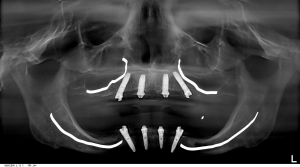

- Bone grafting is avoided by tilting the posterior implants, using available bone (see image below)

This is one of our patients. He had the posterior implants placed to avoid the sinuses on his upper jaw and his implants placed on the lower to avoid the mandibular nerve and mental foramen. This approach means NO BONE GRAFTING! Here, in the picture below, I have outlined the mesial (front) wall of the sinus on the upper, and the mandibular nerve on the lower.

Of course, we want to avoid those structures. I have illustrated how we angled the implants to eliminate the need for bone grafting. We see many patients who are told they need bone grafting in the posterior (back or rear) areas in their mouths because they don’t have enough bone back there. We treat these cases successfully nearly every day without the extensive, expensive, and time-consuming treatment periods. I’ve drawn on the X-ray below where the sinuses and the mandibular nerves are and how we avoid them. This allows us to treat our patients and finish their care, in most cases, in a matter of 3-4 months instead of 12 months or more when bone grafting is done. The All-on-4® treatment concept is a registered trademark of Nobel Biocare services AG.